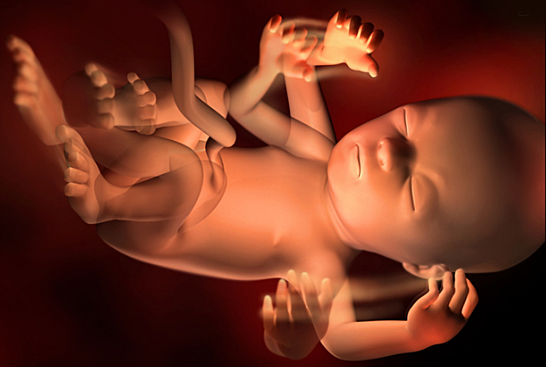

• Semana 32

Semana 32

El bebé pesa en la semana 32 de embarazo entre 1,8 y 2 kilos aproximadamente, y mide entre 38 y 43 centímetros. Ahora se cree que el bebé dentro del útero puede pensar, e incluso crear su primer recuerdo a partir de la semana 32.

• Semana 33

Semana 33

En la semana 33 de gestación,mide unos 43-45 cm y pesa cerca de 2.000 gramos. El cerebro del bebé sigue desarrollándose y ahora ya tiene los cinco sentidos preparados para cuando baya que nacer.

• Semana 34

Semana 34

El bebé mide aproximadamente 46 centímetros y pesa alrededor de 2,200 gramos. Sus pulmones ya están casi completamente formados y sus huesos se han ido endureciendo pero todavía son muy flexibles, incluidos los de la cabeza.Su cráneo todavía no está completamente cerrado, lo cual le permite adaptarse con mayor facilidad al canal de parto en el momento de nacer. Por eso, algunos bebé nacen con la cabeza en forma de cono o aplastada, pero esto se revierte a los pocos días de nacer.